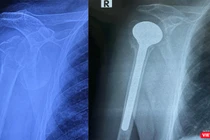

![]() |

| Đã có khoảng 200 trẻ được thụ hưởng chương trình |